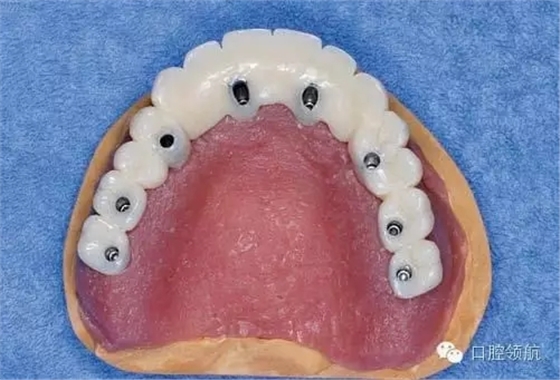

醫(yī)生在制作即刻負重的上部結構時,應把事先做好的臨時上部結構(圖3)先分割開(圖4),再在口腔內分幾次用快速聚合樹脂連接(圖5)。

圖3 事先做好的臨時上部結構。